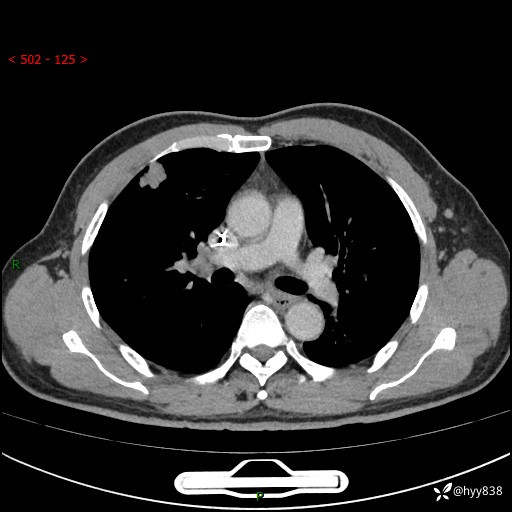

现病史:者10余天前因胸闷就诊于我院心血管内科,行胸部CT提示右肺上叶结节(24mm×16mm),考虑肿瘤性病变可能。无畏寒、发热、盗汗,无咳嗽咳痰,无咯血,无胸痛,无呼吸困难等不适,未予特殊处理。今为求进一步诊治,前来我院就诊,门诊以“肺结节待查”收住入院。 患者自起病来精神、食欲、睡眠尚可,体力下降,体重无明显变化。

胸部CT平扫+增强